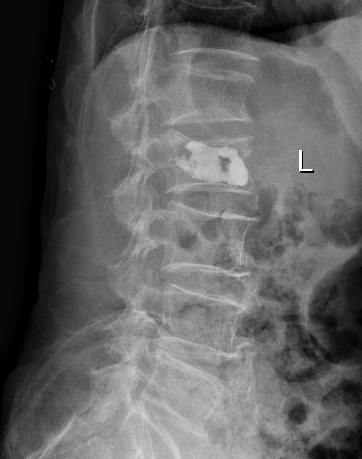

术前

术前